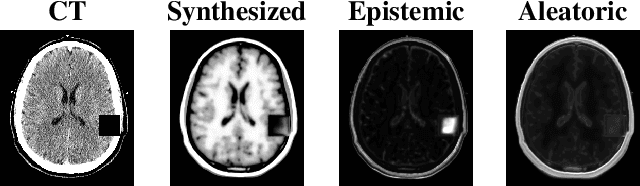

Abstract:Medical images are increasingly used as input to deep neural networks to produce quantitative values that aid researchers and clinicians. However, standard deep neural networks do not provide a reliable measure of uncertainty in those quantitative values. Recent work has shown that using dropout during training and testing can provide estimates of uncertainty. In this work, we investigate using dropout to estimate epistemic and aleatoric uncertainty in a CT-to-MR image translation task. We show that both types of uncertainty are captured, as defined, providing confidence in the output uncertainty estimates.

Abstract:Medical images are often used to detect and characterize pathology and disease; however, automatically identifying and segmenting pathology in medical images is challenging because the appearance of pathology across diseases varies widely. To address this challenge, we propose a Bayesian deep learning method that learns to translate healthy computed tomography images to magnetic resonance images and simultaneously calculates voxel-wise uncertainty. Since high uncertainty occurs in pathological regions of the image, this uncertainty can be used for unsupervised anomaly segmentation. We show encouraging experimental results on an unsupervised anomaly segmentation task by combining two types of uncertainty into a novel quantity we call scibilic uncertainty.